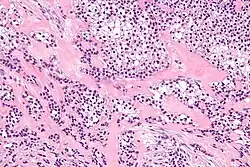

| Micrograph of a hyalinizing clear cell carcinoma showing the characteristic clear cells and surrounding hyalinized stroma. H&E stain. | |

HCCC consist of cells with abundant clear cytoplasm, arranged in cords, trabeculae or clusters in a hyalinized stroma.[3] Nuclear pleomorphism is usually minimal and mitoses are infrequently seen.[2]

Owing to their glycogen content, which explains the "clear" appearance under the microscope, tumour cells stain with PAS. Immunostains for S100 and smooth muscle actin (SMA) are typically negative, but positive for cytokeratins and epithelial membrane antigen (EMA).

Intermed. mag.

Intermed. mag. -